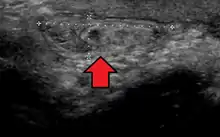

- ↑ Sharma N, Kumar N, Verma R, Jhobta A (2017-05-31). "Tibialis Anterior Muscle Hernia: A Case of Chronic, Dull Pain and Swelling in Leg Diagnosed by Dynamic Ultrasonography". Polish Journal of Radiology. 82: 293–295. doi:10.12659/PJR.900846. PMC 5462483. PMID 28638493.